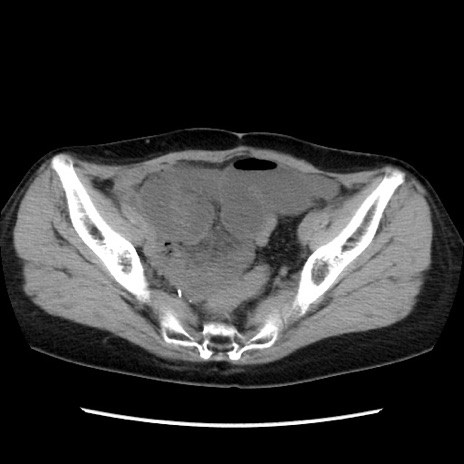

症例32(横断像)

【症例】40歳代 女性

【主訴】上腹部痛、嘔気・嘔吐

【現病歴】約9時間前頃から急に上腹部痛、嘔気、嘔吐が出現。改善しないため救急要請。

【既往歴】子宮頚癌(広汎子宮全摘術、放射線療法)、腸閉塞

【身体所見】腹部:平坦、軟、腸雑音亢進、上腹部を中心に腹部全体に圧痛あり。

【データ】WBC 8400、CRP 0.03